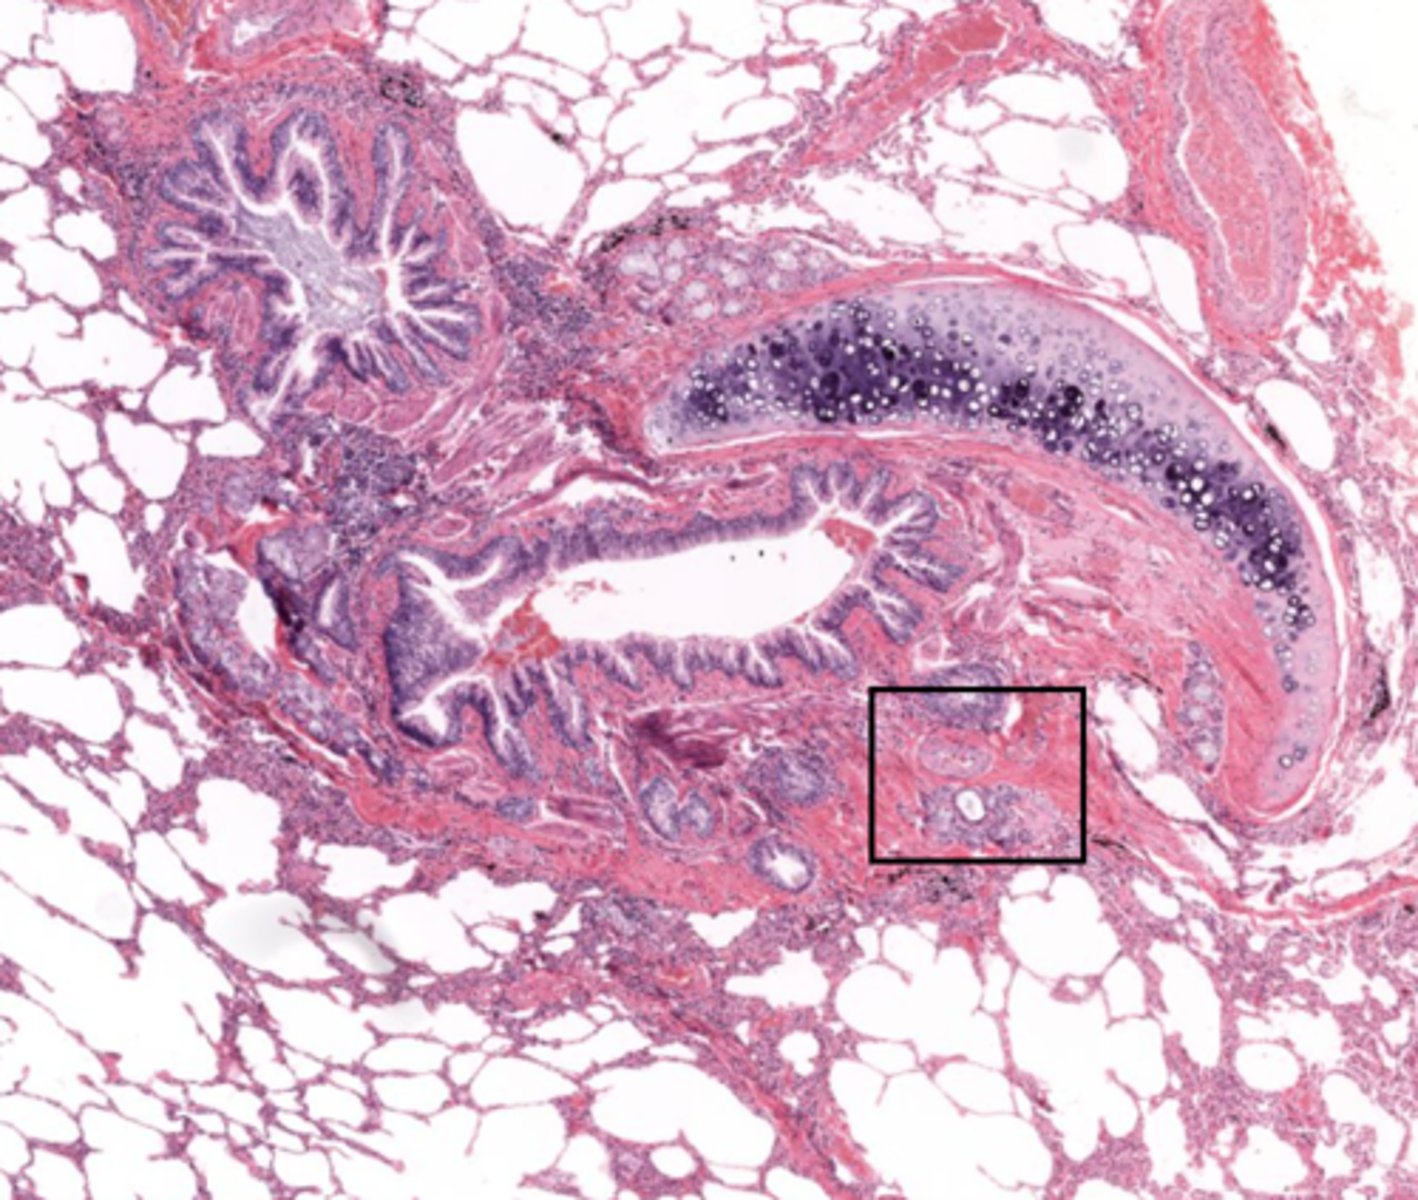

Identify the organ

lungs

Identify the type of airway

bronchi

Identify this type of airway

bronchioles

Identify the type of bronchiole

terminal bronchioles

respiratory bronchioles